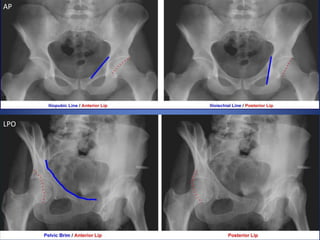

Name the views and the indication for taking

this view…..

Judet Views

Patient supine, oblique patient 45o both ways (RPO & LPO).

Taken to evaluate fractures of acetabulum.

Normal AP view

LPO

AP

RPO